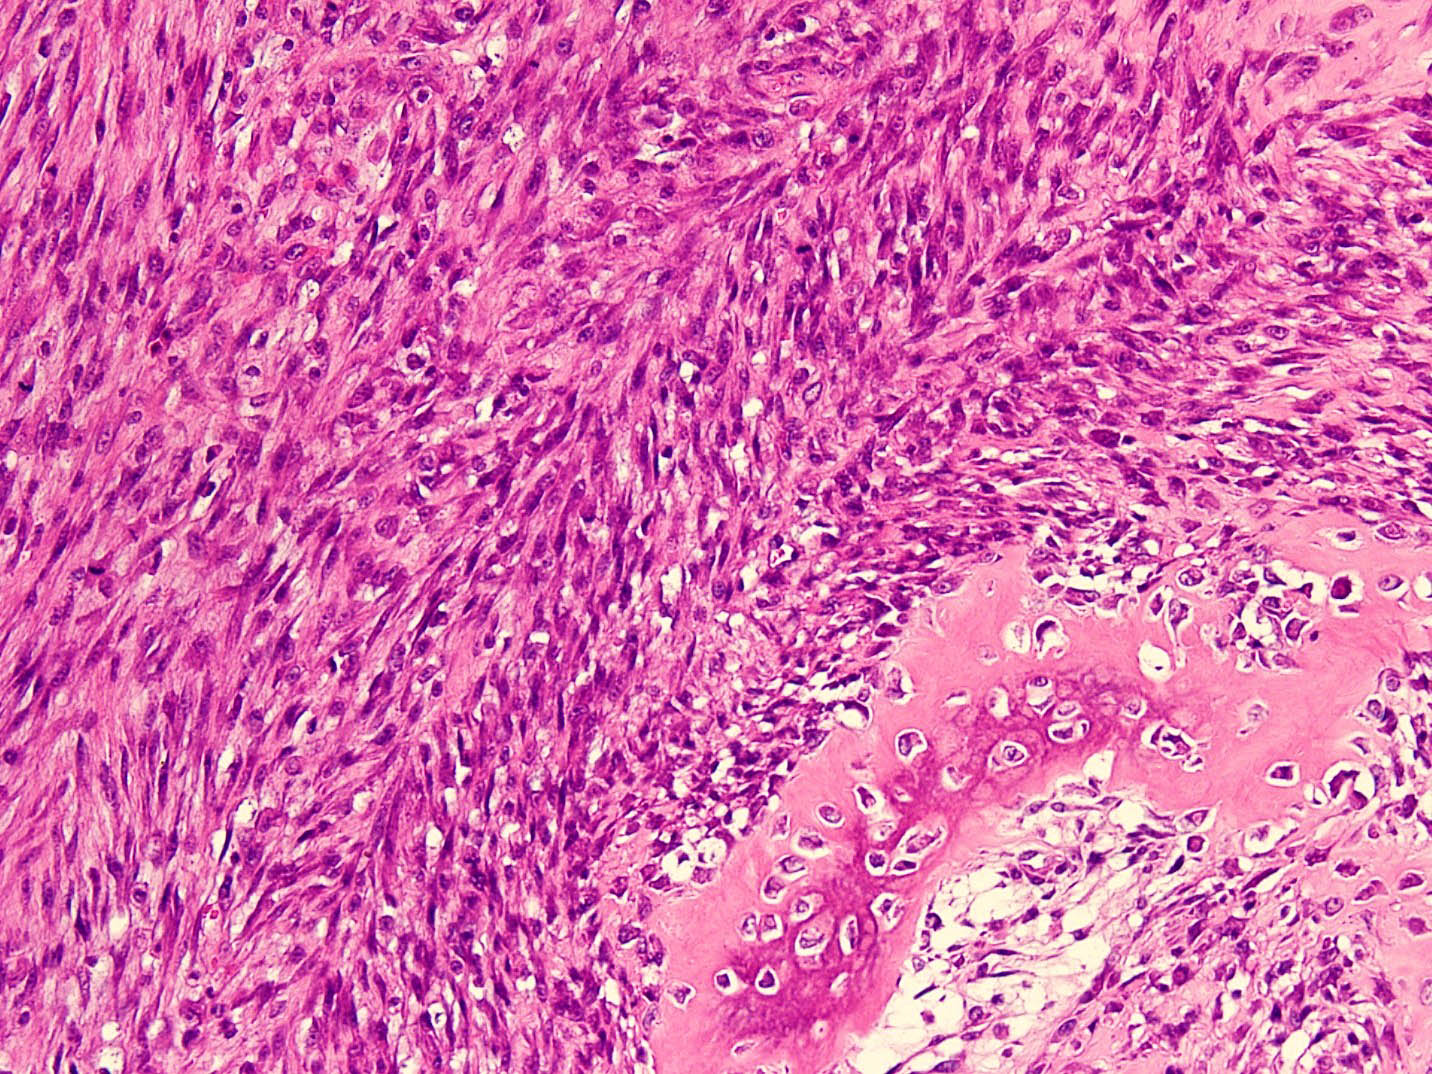

- Histologically, zonal pattern is characteristic with different degrees of cellular differentiation (inner zone, intermediate zone and peripheral zone)

- Inner central zone:

- Composed of fibroblastic / myofibroblastic proliferation, which is richly vascular, rich in inflammatory cells and resembles nodular fasciitis; some multinucleated giant cells may also be seen

- Cells show mild degree of pleomorphism and brisk mitosis

- Areas of hemorrhage, fibrin, endothelial proliferation and entrapped atrophic muscle fibers are noted

- Intermediate zone:

- There is a mixture of fibroblasts and osteoblasts along with erratic osteoid separated by small sized vessels

- Scattered chondrocytes may be appreciated

Microscopic (histologic) images

A 36 year old boxer presented with a painful mass in the right arm for the last 1.5 months. On radiology, an intramuscular mass was seen with peripheral mineralization and central latency. It was biopsied, which showed the morphology in the image above. What is the most likely diagnosis?

B. Myositis ossificans. The given history in this case shows that the patient is physically active and provides short duration history of the lesion. The radiological findings suggest a lesion with maturation at periphery. The microscopic image shows characteristic zonation. These are all features of myositis ossificans.

Biopsy from a thigh mass in a 31 year old man shows a circumscribed lesion rimmed entirely by skeletal muscle and comprised of a haphazard arrangement of spindle cells with mild nuclear pleomorphism, prominent nucleoli and increased mitotic figures. The background is highly fibrovascular and shows extravasated red blood cells, inflammatory cells and myxoid change. At the advancing edge of the lesion, there is focal, mature lamellar bone present. What is the likely diagnosis?

B. Myositis ossificans. The question describes a detailed microscopic description of myositis ossificans. The lesion is not osteosarcoma because it is circumscribed and shows zonation in the form of mature periphery and immature center. This is contrary to osteosarcoma. Nodular fasciitis does not show heterotopic ossification and zonal pattern, although the center of myositis ossificans is reminiscent of nodular fasciitis.